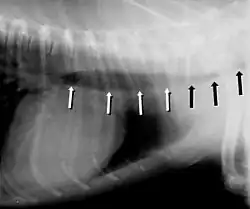

Tracheal stent in a dog

Symptoms include a cough (often called a "goose honk cough" due to its sound), especially when the dog is excited. This cough is usually paroxysmal in nature. Other symptoms include exercise intolerance, respiratory distress, and gagging while eating or drinking. Tracheal collapse is easily seen on a radiograph as a narrowing of the tracheal lumen. Treatment for mild to moderate cases include corticosteroids, bronchodilators, and antitussives. Medical treatment is successful in about 70 percent of tracheal collapse cases.[4] Severe cases can be treated with surgical implantation of a tracheal stent (inside or outside of the trachea) or prosthetic rings. Extraluminal (outside the trachea) stenting is generally used only for tracheal collapse in the neck region. Intraluminal stenting has shown more promise for success with intrathoracic cases, especially using nitinol, a type of shape memory alloy composed of nickel and titanium. Potential problems include stent migration and fracture.[5]